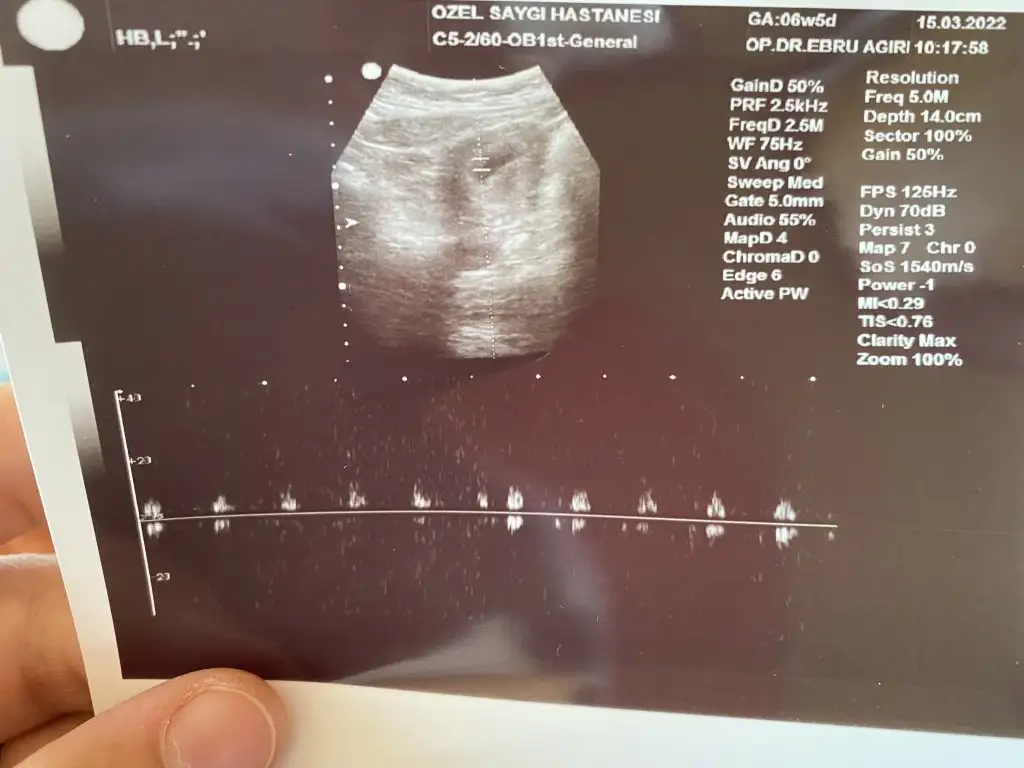

Hepsi vajinal ultrason.

Sırayla 6+5, 7+0, 8+6 hafta görüntüleri. Merakla yorumunuzu bekliyorum 🤩

5F5A868D-D889-45DC-A5F4-9B0753694059.webp

595F5D4B-6C39-4F72-98F6-1146AB445D16.webp

ABAEEA7E-612A-4234-A9CF-137C63FB60C1.webp